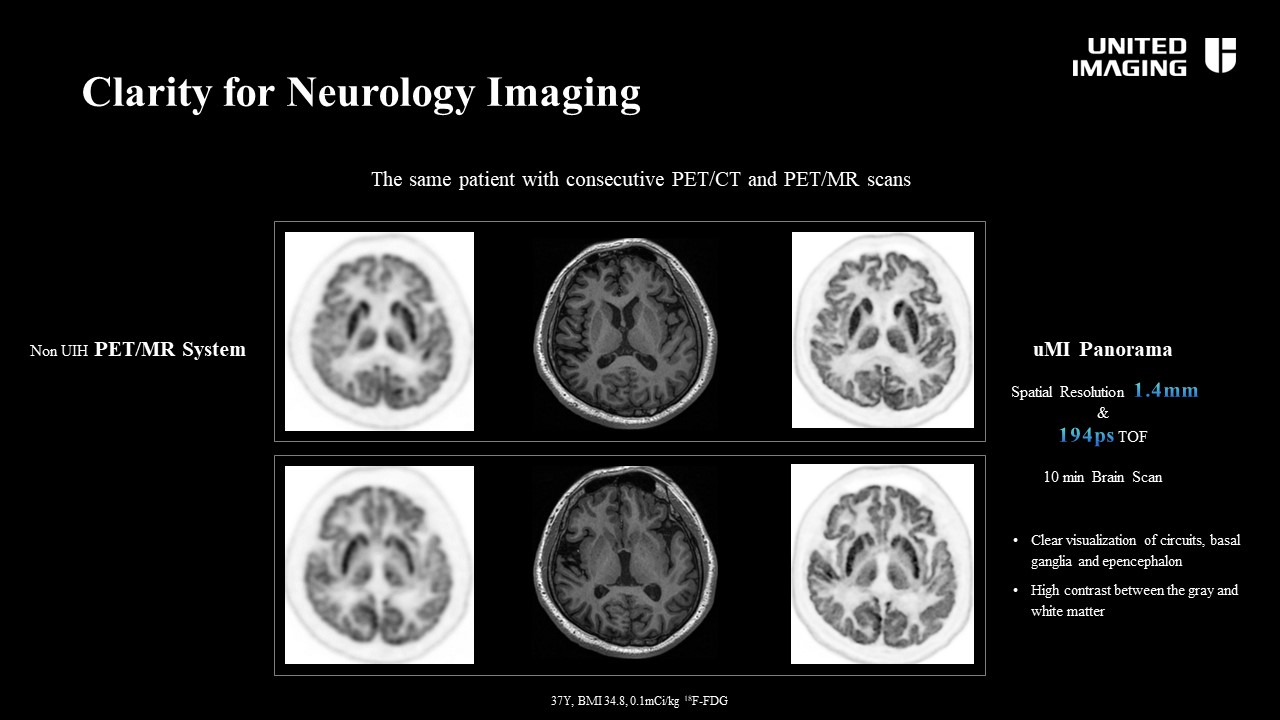

uMI Panoramaは従来のUnited Imaging 社製PET/CT装置uMI780、uMI550と同様2.76mm×2.76mmのLYSOクリスタルによる空間分解能2.9mmと高分解能を維持しつつ、TOF時間分解能を194psまで高めることにより、実効感度143cps/kBqを実現した高分解能と高感度を両立したPET/CTです。